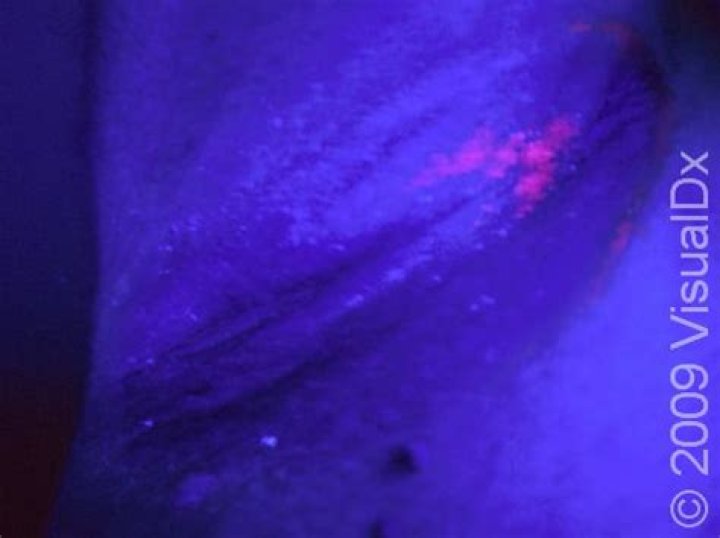

By using black light to illuminate areas of the skin surface, medical professionals can easily see the presence of bacteria and fungi, which cause affected skin areas to change color under the light.

Normally, the light will look purple or violet and your skin will not fluoresce (glow) or show any spots under the Wood's lamp. Your skin will change color if you have a fungal or bacterial, as some fungi and some bacteria naturally luminesce under ultraviolet light.

What does fungus look like under a blacklight?

These areas will have sharper borders under black light and will look bright blue-white or yellow-green. Ringworm. Like tinea capitis, ringworm, or tinea corporis, is a skin infection caused by a fungus. It's a red, itchy, circular rash that gets its name from its appearance.

A Wood lamp examination is a test that uses ultraviolet (UV) light to look at the skin closely. A Wood's lamp is a light that uses long wave ultraviolet light. When an area of scalp that is infected with tinea (a type of ringworm fungus) is viewed under a Wood's light, the fungus may glow.

Using light is a simple way to detect ringworm, although not the only way. The color of ringworm under a Woods Lamp is a bright apple green, which may show under a blacklight with a blue filter in a darkened room.